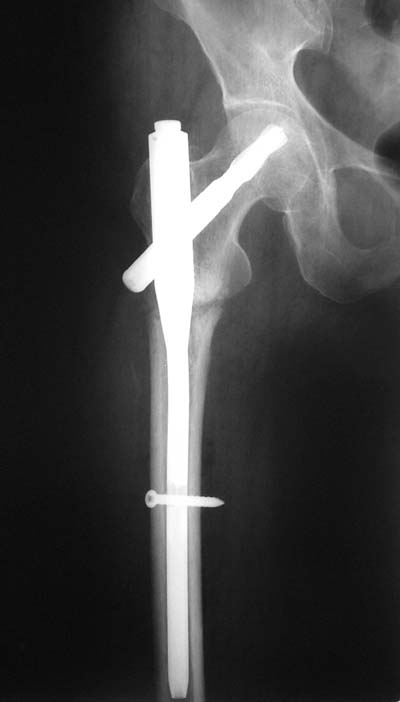

Да? Качество рентгенограмм конечно неочень, но ведь это нестабильный перелом 31.А2.2, не так ли?

Не думаю так. см вложение.

> Да? Качество рентгенограмм конечно неочень, но ведь это

> нестабильный перелом 31.А2.2, не так ли?

Ну, после помещения туда такого гвоздя даже без дистального винта заметной нестабильности уже не остается ;-)